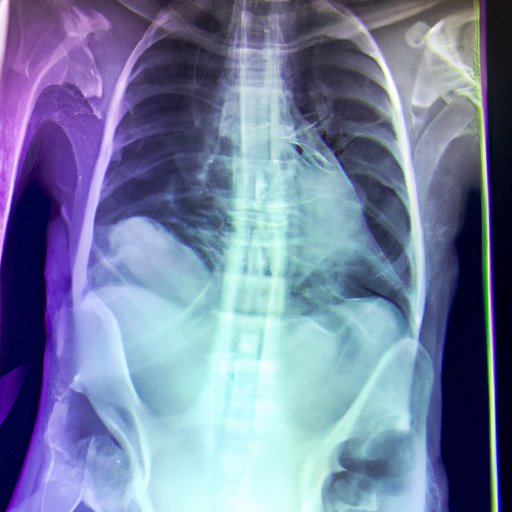

Röntgen’s discovery of the X-ray was a major breakthrough in the field of physics and chemistry. To understand how he was able to create the first X-ray image, it’s important to explore the science behind the process. X-rays are a type of electromagnetic radiation, similar to visible light, but with much higher energy levels. When this radiation passes through matter, such as the human body, it is absorbed by certain tissues and produces a dark shadow on the film or screen.

This absorption of X-rays is dependent on the density of the material. For example, bones absorb more X-rays than soft tissue, creating a darker shadow on the film. By manipulating the intensity of the X-rays and the exposure time, Röntgen was able to create the first X-ray image.